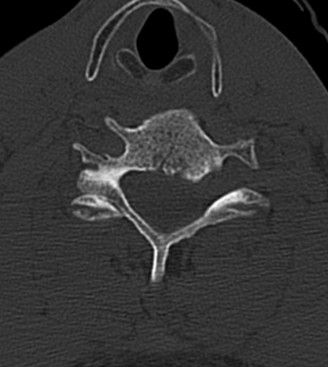

Determine the most appropriate treatment of different types of Hangman’s fractures? CASE 14 A 70-year-old retired, funeral director presents with symptoms of right upper extremity numbness and weakness. He reports that he developed acute neck and right upper arm pain while undergoing a dental procedure. Treatment so far has been nonsteroidal anti-inflammatory medication and physical therapy with cervical traction. While his pain improved with this course of treatment, he has ongoing paresthesias radiating into his right hand and weakness affecting his right upper extremity. Figures 1–20 and 1–21 show a midsagittal and axial image through C6–7, respectively.

The correct answer is (A). Considering the patient’s complaints and the imaging, he most likely has radiculopathy, probably secondary to a disc-osteophyte complex associated with foraminal stenosis at the C6–7 level. There is no suggestion in the history of walking imbalance or dexterity issues in the upper extremities. Thus, a diagnosis of myelopathy is less likely. Furthermore, the degree of spinal compression is mild and not likely (though not impossible) to cause spinal cord dysfunction. An intradural tumor would have a different MRI appearance, likely demonstrating an area of high signal within the parenchymal tissue of the spinal cord itself. A central cord syndrome is an acute spinal cord injury with upper extremities being affected more than lower extremities.

The correct answer is (C). The patient has nerve root compression at the C6–7 level, which would affect the exiting C7 nerve. Weakness of right elbow extension and wrist flexion with sensory loss of the middle finger are the most likely findings.

The correct answer is (D). Both anterior and posterior surgical approaches have been associated with consistently good clinical outcomes in this patient population having single level radiculopathy from foraminal stenosis secondary to a disc-osteophyte complex. Objectives: Did you learn...? Recognize the clinical presentation of cervical radiculopathy associated with a disc-osteophyte complex?